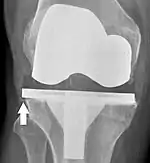

Knee replacement is routinely evaluated by X-ray, including the following measures:

- FFC: frontal femoral component angle. It is typically regarded as optimal when being 2–7° in valgus.[56]

- FTC: frontal tibial component angle, which is regarded as optimal when being at a right angle. A varus position of more than 3° has generally been found to increase the failure rate of the prosthesis.[56]

- Anterior femoral notching (the femoral component causing reduced thickness of the distal femur anteriorly), seems to cause an increased risk of fractures when exceeding about 3 mm.[57]

- LTC: lateral (or sagittal) tibial component angle, which is ideally positioned so that the tibia is 0–7° flexed compared to at a right angle with the tibial plate.[56]